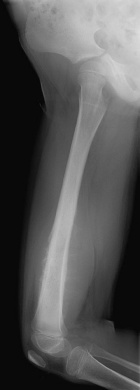

M.D. - 5 year old female with right thigh pain for one month, her parents have noticed swelling in her thigh over the past week, she began limping a few days ago and now is reluctant to bear weight on her right leg